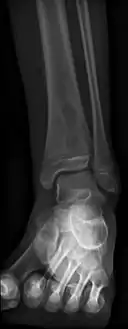

Radiographic features

Oval, elliptical, or serpentine radiolucency usually greater than 1 cm surrounded by a heavily reactive sclerosis, granulation tissue, and a nidus often less than 1 cm. The margins often appear scalloped on radiograph. Brodie's abscess is best visualized using computed tomography (CT) scan. Associated atrophy of soft tissue near the site of infection and shortening of the affected bone. Osteoblastoma may be a classic sign for Brodie's abscess.

Periostial reaction along the medial cortex indicates an aggressive lesion. Neoplasm such as Ewing sarcoma and osteomyelitis could both have this plain radiographic appearance. Staphylococcus was recovered at surgery.